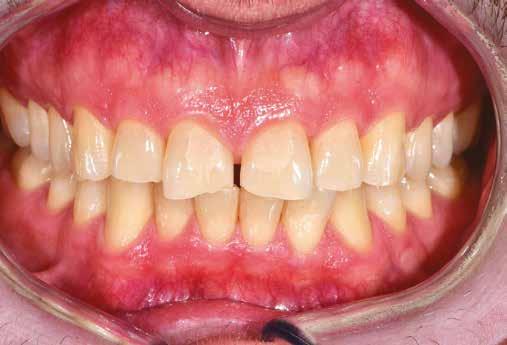

A rendelésünkön egy 34 éves latin-amerikai nőbeteg azzal a panasszal jelentkezett, hogy a fogait „túl rövidnek” találja, és ezen felül a mosolyával sem volt megelégedve. Az anamnézisfelvétel alapján egészséges volt, elmondása szerint rendszeresen járt orvoshoz. Öt évvel korábban néhány hátsó fogát restaurálták. Páciensünk szájhigiénéje megfelelő volt,

a fogait rendszeresen ápolta. House klasszifikációja szerint, amely a pácienseket a fogászati kezelésekhez való attitűdjük szerint négy csoportba sorolja, a páciensünk a szabálykövető csoportba tartozott.

Az előzetes állapotfelmérést és a kezelés megtervezését követően a fogakat minimál invazív módon preparáltuk (1. a-b ábrák), majd az előkészített fogak ínybarázdáiba fonalbehelyező eszköz segítségével (113 Serrated Gingival Cord Packer, Hu-Friedy, Chicago, Illinois) teflonszalagot helyeztünk (Loctite Thread Seal Tape, Henkel Loctite Corp., Egyesült Államok), (1. c ábra). A hagyományos retrakciós fonalak helyett, a rugalmasságuk miatt előnyösebbnek tartjuk a teflonszalagok használatát. A kofferdámot (Dental Dam, Nic Tone, Bukarest, Románia) az előkészített fogakon kívül, az azoktól disztálisan elhelyezkedő egy-egy fognak megfelelően is perforáltuk.

A rendelésünkön jelentkező 40 éves nőbeteg a mosolyának esztétikai megjelenésén szeretett volna javítani (1. ábra)

A vizsgálat során a jobb felső első kisőrlőfog (1,4) és a bal felső első kisőrlőfog (2.4), valamint a köztük elhelyezkedő fogak kifejezett mértékű kopását észleltük (14-24). Ezen felül a felső metszőfogak (1.2–2.2) élei egyenetlen lefutással rendelkeztek, és a jobb felső nagymetszőfog (11) – amelyet korábban gyökérkezeltek és kompozit töméssel láttak el –jelentős színbeli eltérést mutatott. Az 1.4-es és 2.4-es fo-